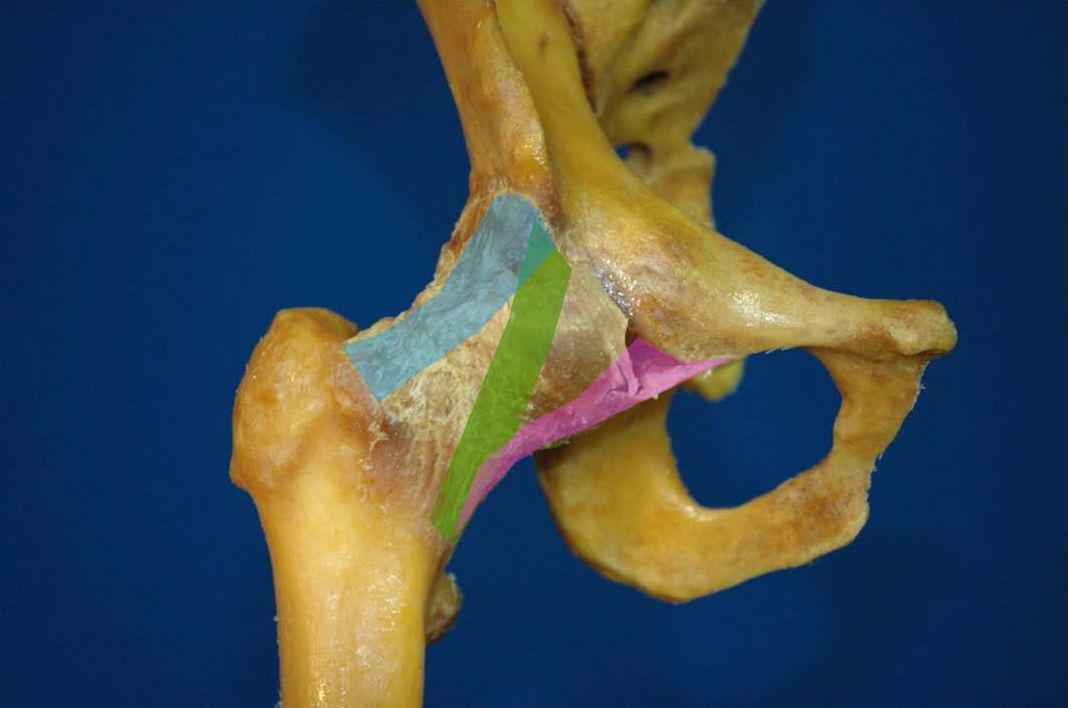

Joint capsule (Fig. 3)

The hip has the most solid joint capsule in the entire body. It has four ligaments, each of which stabilize the joint in different positions. These three ligaments wrap around the femoral neck and give the capsule a spiral shape which tightens in extension, encourages the circulation of synovial fluid into the cavity, and creates natural fixation of the joint (15, 16). When examining a patient for instability, the hip should be placed in extension.

The iliofemoral ligament or (Y ligament) is the strongest in the body. Its upper fibres arise from the anterior inferior iliac spine just beneath the origin of the rectus femoris tendon. The lateral band attaches in front of the greater trochanter onto the trochanteric tubercle. The medial band wraps around the femoral neck and attaches just above the lesser trochanter. Its role is to restrict external rotation of the hip in flexion. When the hip is extended, it restricts external and internal rotation. The lower portion of the ligament just above the calcar and lesser trochanter merge with the fibres of the medial located pubofemoral ligament. The pubofemoral ligament originates from the anterior inferior acetabulum. Its main role is to restrict external rotation of the hip in extension. The ischiofemoral ligament starts at the ischial acetabular margin and wraps around the femoral neck behind the joint. Its role is to limit posterior translation and internal rotation in both flexion and extension (17). The zona orbicularis is a capsular thickening encircling the femoral neck and limits femoral head distraction.